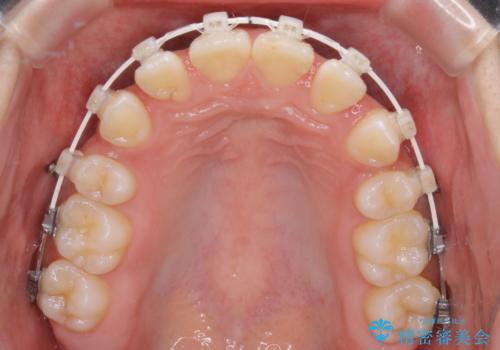

- 矯正装置

- 審美装置(ワイヤー)

- 治療期間

- 1年10ヶ月

- 出っ歯が気になるとご相談にいらした方です。抜歯して歯を並べました。深かった噛み合わせも改善させることが出来ました。